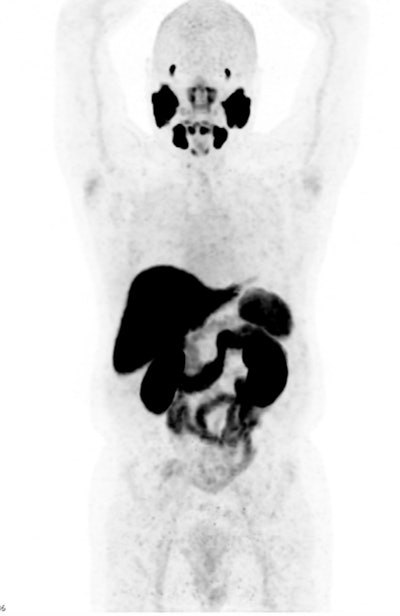

Normal radiotracer distribution for F-18-PSMA.

To accurately interpret nuclear medicine studies, a knowledge of the normal physiological distribution of the radiotracer is required. PSMA expression is present in normal prostatic tissue, though at a low level, and can also be found in the salivary and lacrimal glands, nasal cavity, larynx, liver, spleen, intestines, kidneys, and sympathetic ganglia, the authors pointed out.

The first F-18-PSMA-1007 PET study was performed at the Mater in April 2022. The patient had been diagnosed with prostate cancer more than a decade earlier, having multiple nodal, lung, and bone metastases. Despite ongoing treatment with gonadotrophin-releasing hormone agonists, his prostate-specific antigen (PSA) was continually rising.